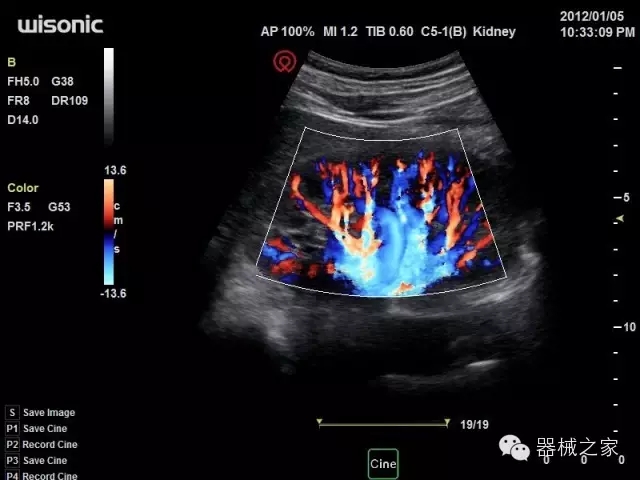

經(jīng)典產(chǎn)品:四葉草

臨床圖片賞析

產(chǎn)品特點(diǎn)

·全球目前唯一一款配備主機(jī)雙探頭接口,整機(jī)重量(含電池)在5公斤以內(nèi)的便攜式彩超;

·一款互聯(lián)網(wǎng)彩超,只要有手機(jī)信號(hào)的地方就可以非常方便地實(shí)現(xiàn)遠(yuǎn)程會(huì)診和病案調(diào)取;

·獨(dú)有的HoloTM PW 實(shí)時(shí)3取樣門(mén)PW成像技術(shù),精確進(jìn)行血管診斷;